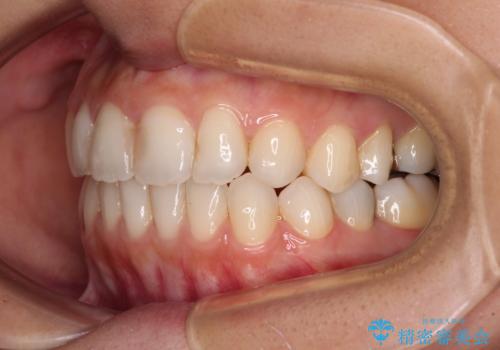

- オープンバイトのため、話しているときの見た目が気になるとのことで来院された患者様です。

下顎骨は左側にシフトしており、咬み合ったときには奥歯と前歯の一部しか接触していない状態でした。

骨格的な左右差は歯列矯正は改善できないため、上下歯列が全体的に接触することをゴールとしてインビザラインにて矯正治療を行うこととしました。

前歯のデコボコの解消と並行して上下の奥歯を圧下させるようにすることで、前歯を接触させるように計画しました。

上下の隙間に舌が入り込むことがオープンバイトの原因であったため、舌の筋肉のトレーニングも並行して行い、後戻りの抑制を図りました。